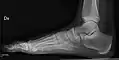

• Ankle - AP/Mortice and Lateral

• Calcaneum - Axial and Lateral

• Foot / Toes - Dorsoplantar, Oblique and Lateral.[19]